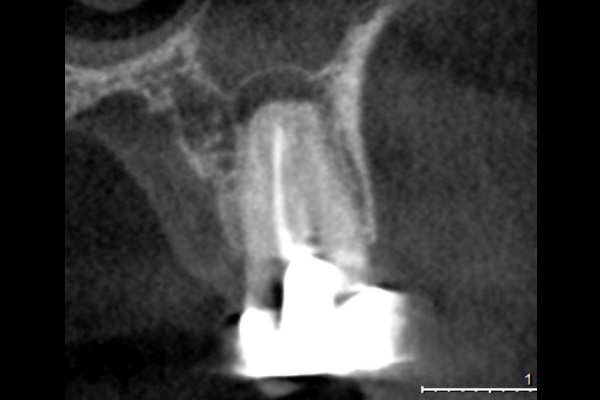

60代男性の大臼歯(奥歯)の症例

- 主訴

- 「時々歯茎が腫れる」とのことでご来院されました。数週間前から症状があり、他の医院では「抜歯の可能性がある」と言われ、不安に感じていらっしゃいました。

- 期間

- 治療期間2ヶ月、治療回数3回、レントゲン写真で治癒を確認できるまでの期間6ヶ月

- 治療内容

- 1.古い被せ物の除去と虫歯の徹底除去 まず、古い銀歯を外し、内部に広がっていた虫歯を丁寧に取り除きました。

2.マイクロスコープ下での根管治療 唾液などによる細菌の侵入を防ぐ「ラバーダム」を装着し、マイクロスコープ(歯科用顕微鏡)で根管内を数十倍に拡大しながら治療を進めました。複雑な形状の根管の内部まで、汚染された組織を徹底的に洗浄・消毒します。

3.根管充填(こんかんじゅうてん) 根管内が完全にクリーンになったことを確認し、再感染を防ぐために専用の薬剤で隙間なく密閉しました。

4.土台と被せ物の作製 歯の強度を補うための土台を立て、最終的なセラミックの被せ物を作製し、装着しました。

- 治療に伴うリスク

- 少しでも汚染物質が残ると再発のリスクが高まります。